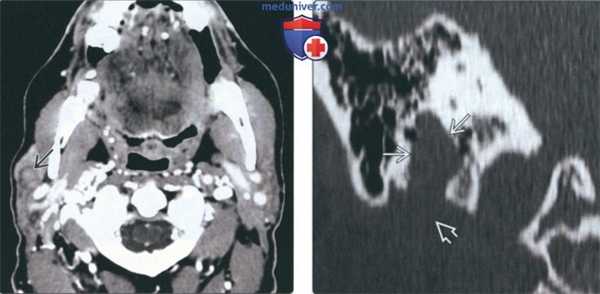

(Справа) МРТ Т2ВИ FS, аксиальная проекция. Визуализируется округлое образование с неоднородным сигналом высокой интенсивности, которое расположено в области переднего края поверхностной доли околоушной железы. Отличить такое образование от доброкачественной смешанной опухоли, которая встречается гораздо чаще, практически невозможно. (Слева) КТ с КУ, аксиальная проекция, выполненная у пациента с нейрофиброматозом 2 типа. В области переднего края поверхностной доли околоушной железы имеется округлое образование размером менее 1 см. Шваннома неравномерно накапливает контраст, но из-за небольших размеров участки кистозного перерождения отсутствуют.

(Справа) КТ в коаном окне, коронарная проекция. Вертикальный сегмент канала лицевого нерва расширен. Шваннома лицевого нерва из облааи околоушной железы распроараняется в шилососцевидное отвераие.

(Слева) На аксиальной КТ с КУ у пациента с нейрофиброматозом 2 типа в передних отделах поверхностной доли околоушной железы визуализируется округлое объемное образование субсантиметрового диапазона. Эта шваннома неравномерно накапливает контраст, кистозные участки в ней отсутствуют из-за малого размера.

(Справа) Накорональной КТ в костном окне определяется равномерное вздутие вертикального сегмента лицевого канала. Шваннома лицевого нерва поднимается через околоушную железу к шилососцевидному отверстию.